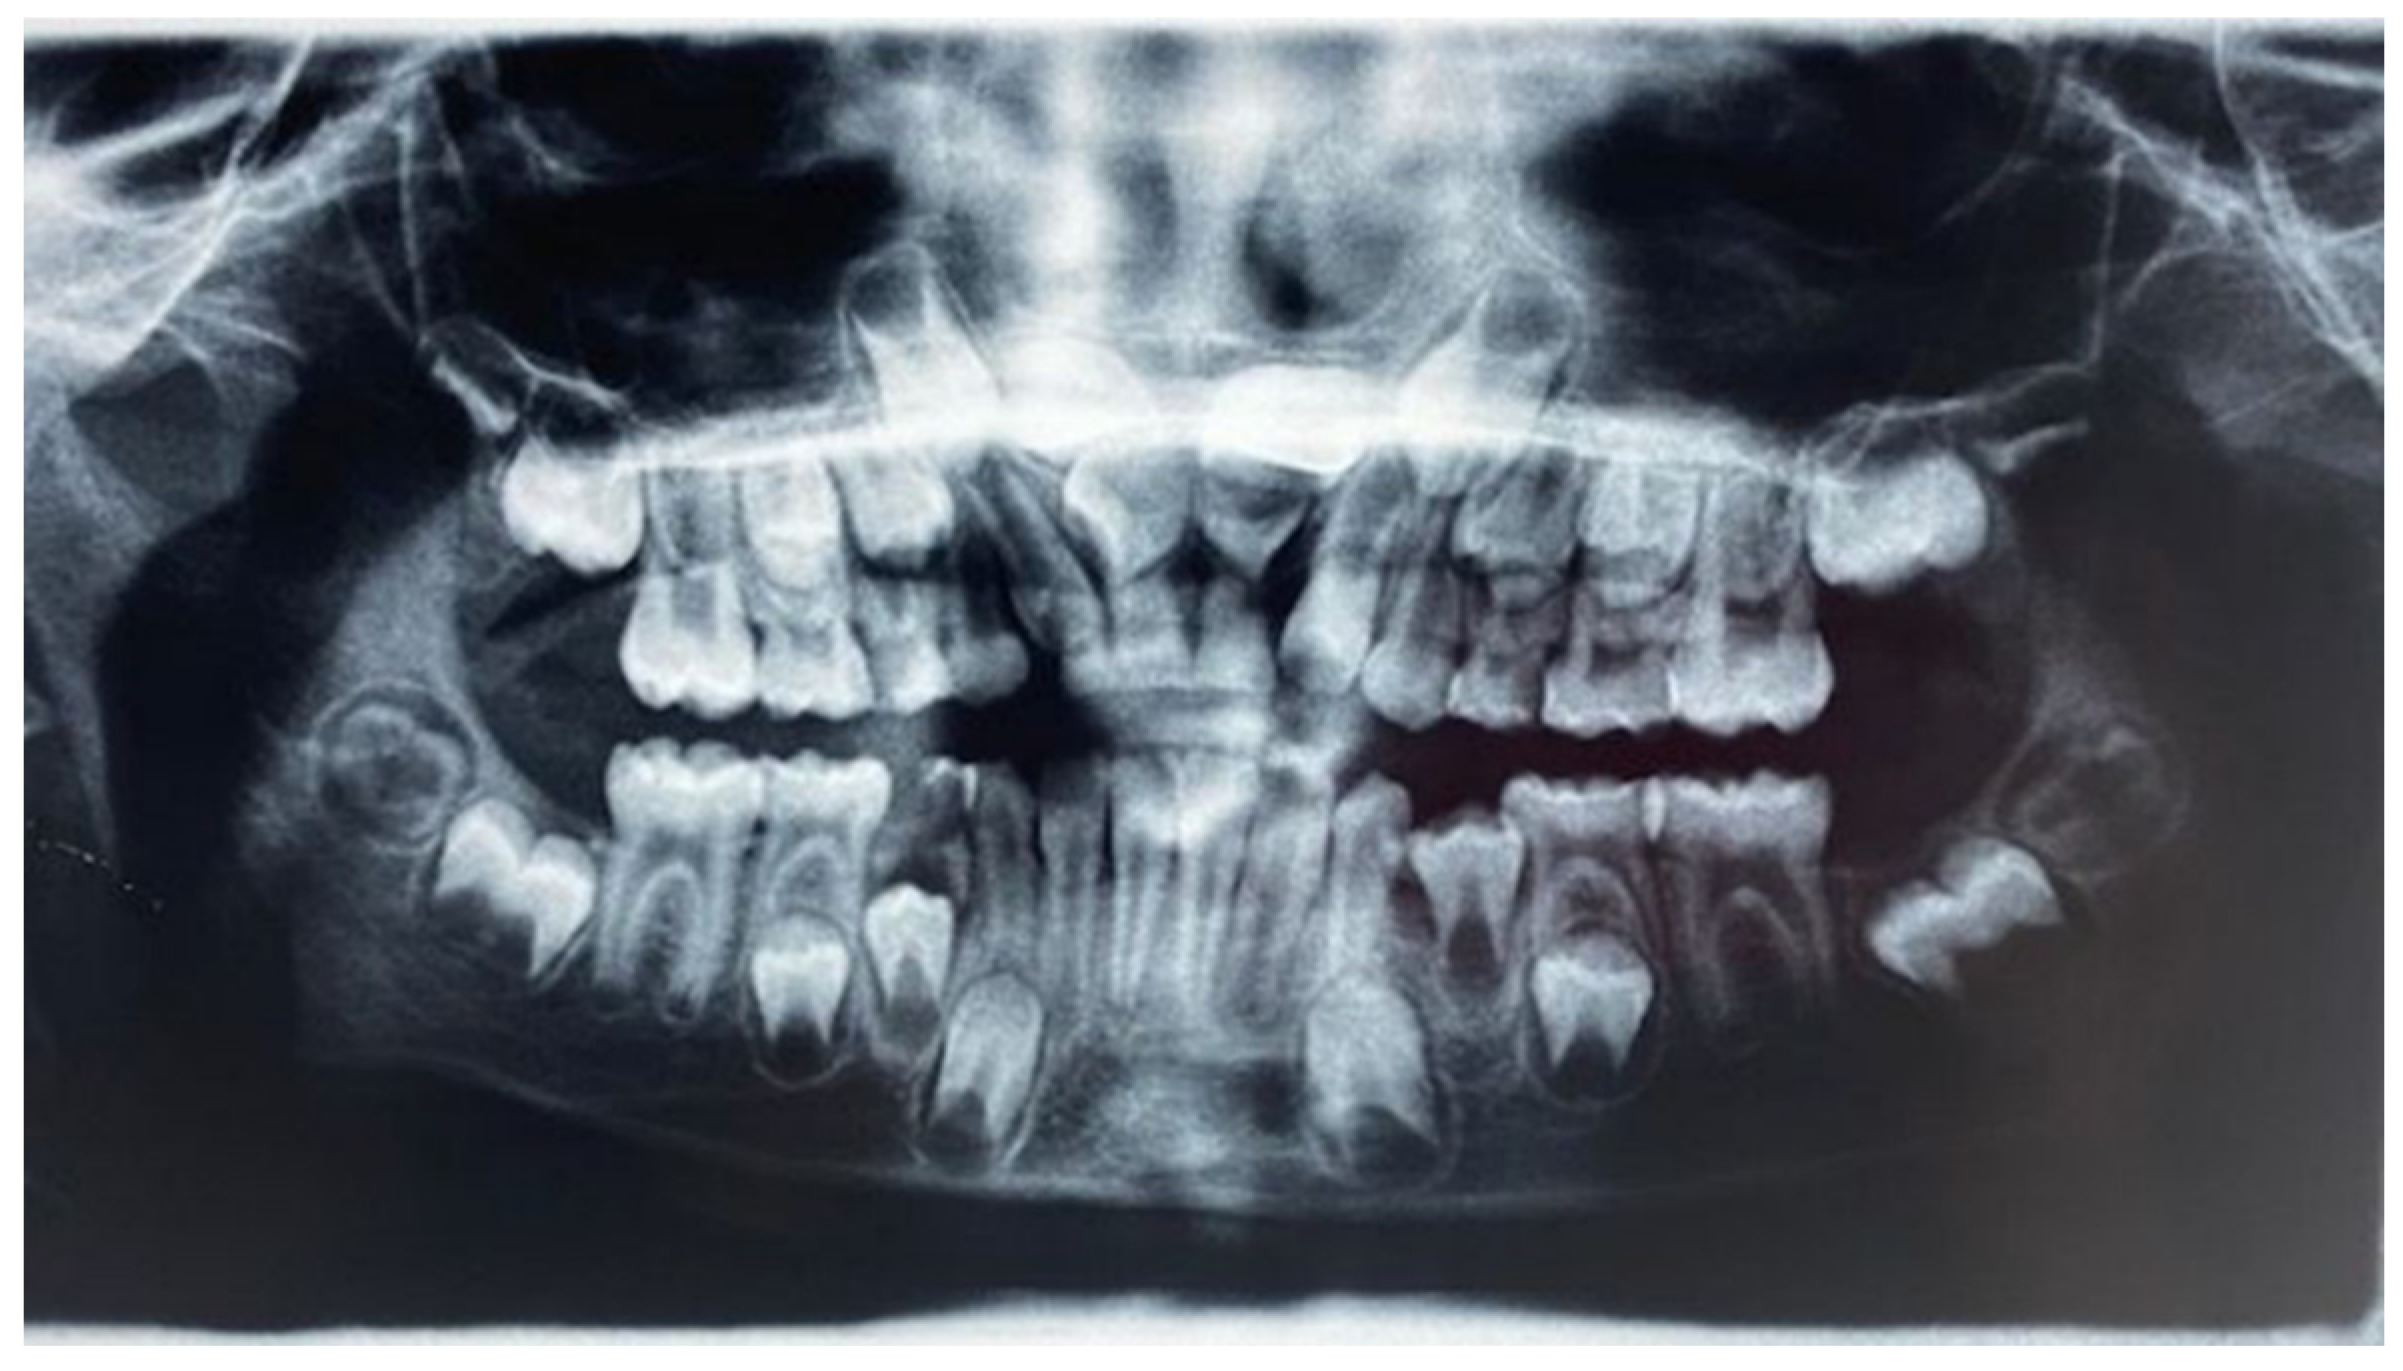

From www.mdpi.com

Applied Sciences Free FullText Impacted Central Incisors in the Extra Teeth In Upper Jaw Did you know that it was possible to have extra teeth in your mouth? Around 98% of the time, hyperdontia patients have extra teeth growing in the upper jaw. Up to 3.8% of people have one or more extra (supernumerary) teeth. An extra tooth can be visible (erupted) or impacted. These extra teeth are sometimes called supernumerary teeth. They can. Extra Teeth In Upper Jaw.